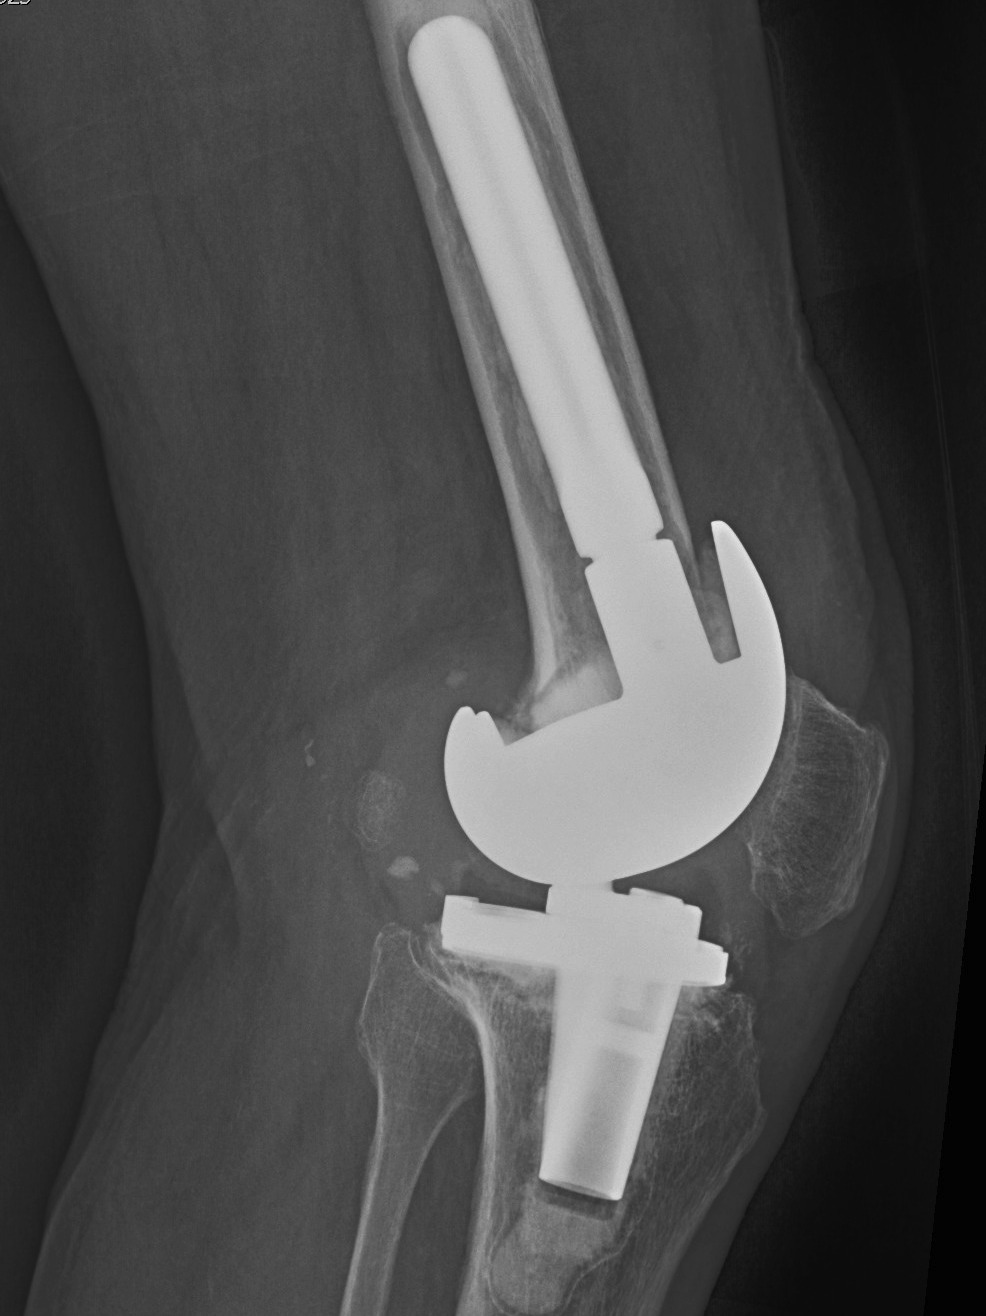

B. Tantalum cones metaphyseal filling / Trabecular metal

Meneghini et al JBJS Am 2009

- tantalum porous tibial implant in 15 pateints followed average 3 years

- AORI type 3 and type 2B

- knee society score average 85

- all had evidence osteointegration, no loosening

Howard et al JBJS Am 2011

- femoral tantalum components in 24 knees followed for averag 3 years

- knee society score average 81

- all well fixed with no complications